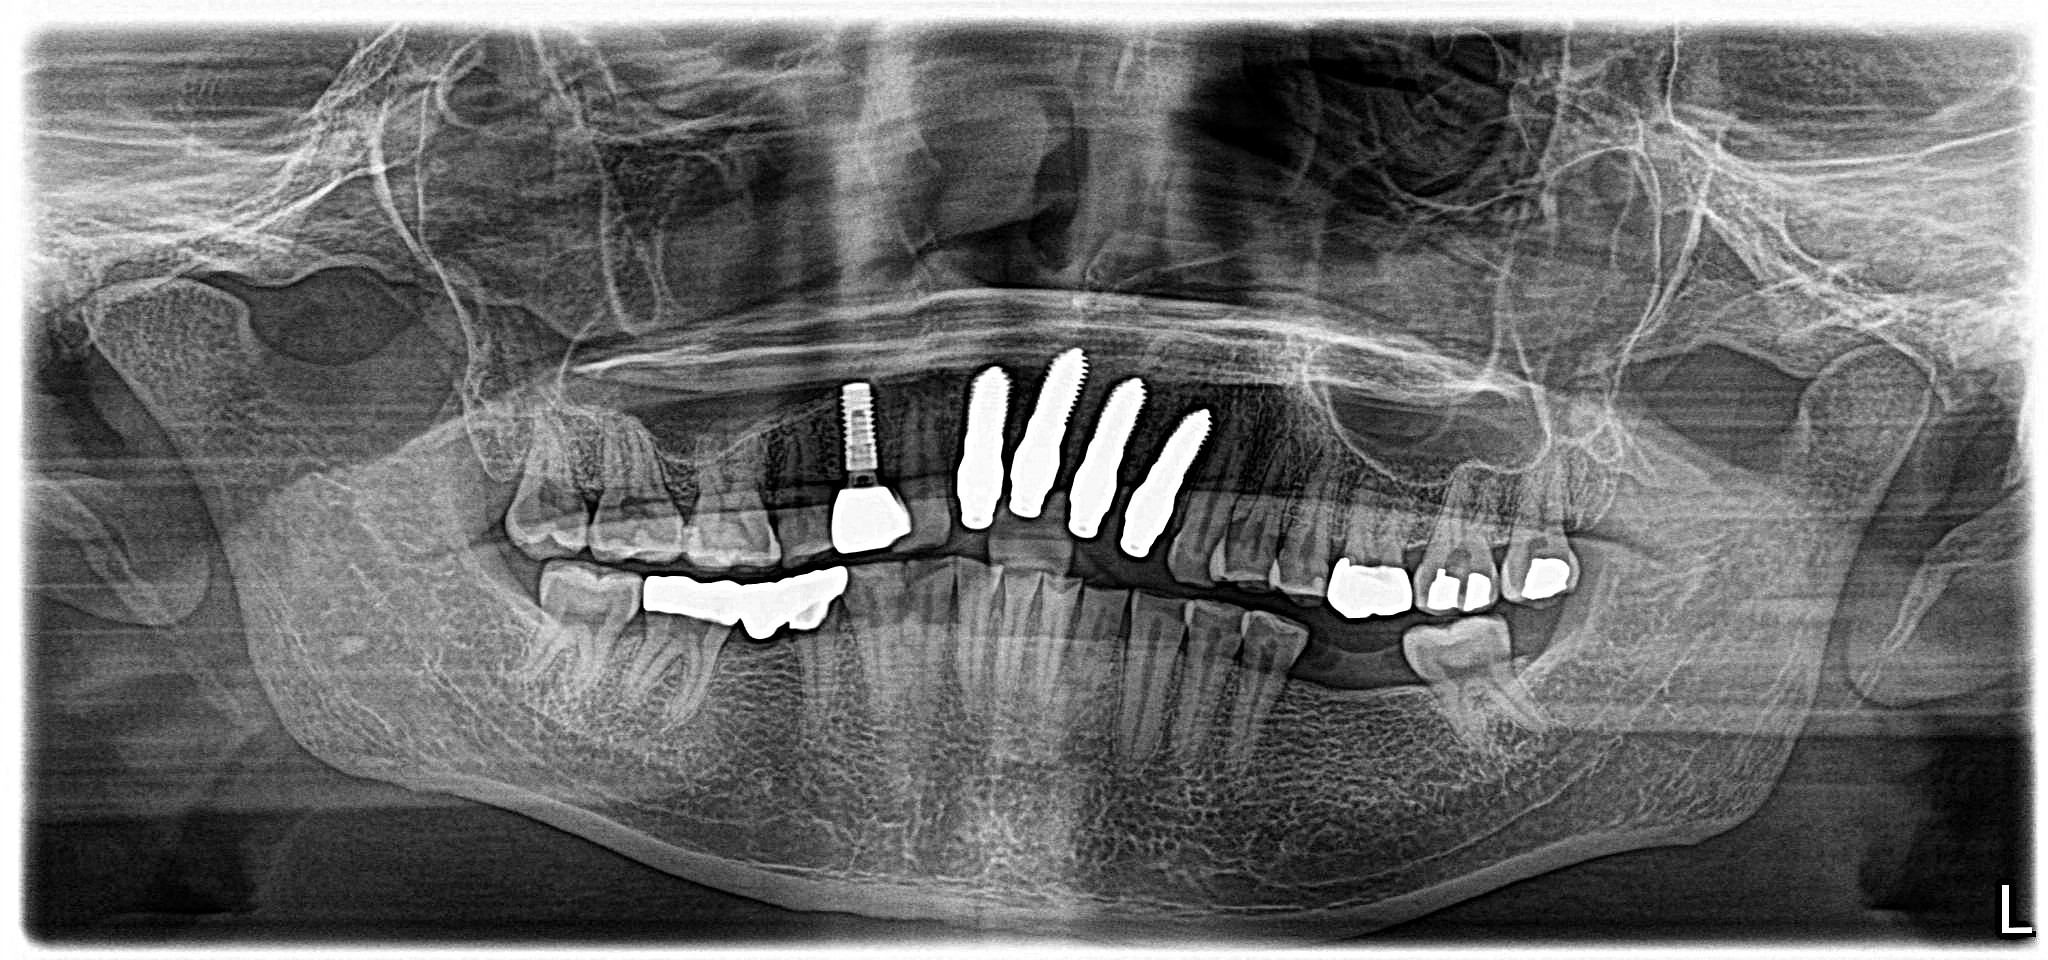

November 18, 2023Updated imaging and comprehensive treatment planning for extraction, guided bone regeneration (GBR), and future implant-supported restoration.

- Detailed diagnostic work-up, including imaging and structural assessment, to confirm that teeth #7–10 were unrestorable due to subcrestal fractures and caries.

- Implant planning and placement based on three-dimensional positioning for long-term stability, proper load distribution, and natural emergence profiles.